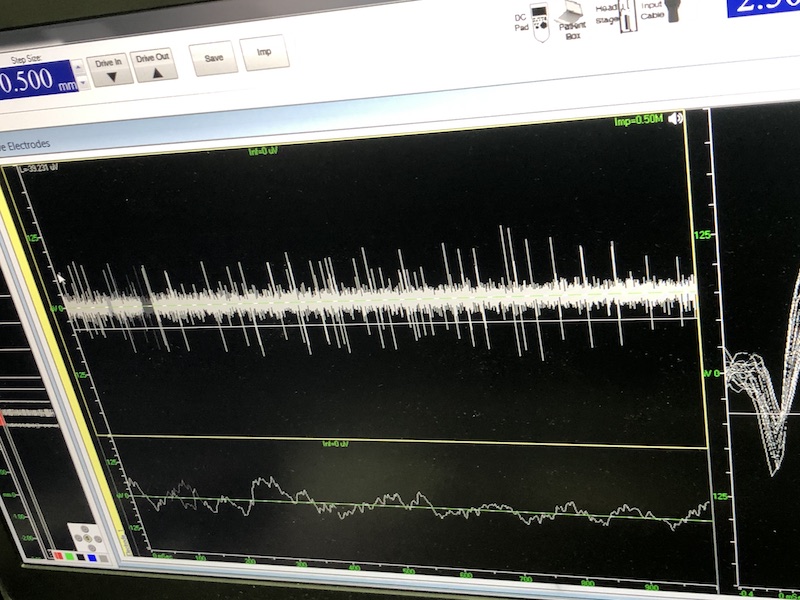

與此同時,檢測電極實時記錄電極末端每一點處的電信號,當(dāng)電極逐漸接近手術(shù)規(guī)劃靶點時,借助電信號的特征,醫(yī)生可以判斷電極是否已經(jīng)沿長軸植入患者顱內(nèi)的目標核團,以及植入的準確長度。下圖中,檢測信號屬于典型的核團信號,證明電極已經(jīng)抵達相對理想的植入位置,記錄下此刻的位置后,即可在相應(yīng)位置植入刺激電極。

檢測核團信號